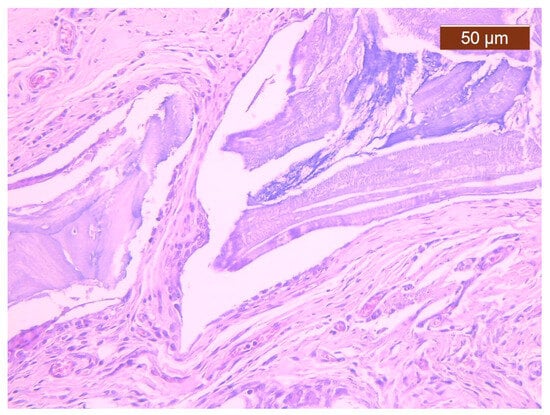

In cases from the BS group, impaired healing was most commonly observed as the persistence of multiple devitalized bone fragments that induced a lymphoplasmacytic inflammatory reaction, which associated the giant cell reaction to the bone substitute used (Figure 2). At 8 weeks, the healing process was present as a fibrous callus that encompassed the bone fragments and joined the two free, post-fracture bone ends. Structurally, the callus consisted of collagen fibres that included fibrocytes that were more frequently identified compared to fibroblasts (which indicated a reduced metabolic activity and, consequently, delayed healing), often capillaries and lymphocytes. Overall, callus progression was related to a decrease in the vessel count within the initial fibro-vascular callus to facilitate the remodelling of cartilage and bone.

Figure 2. Fibrous callus displaying multiple capillaries, a giant cell reaction to Bio-Gen® bone graft fragments, and rare lymphocytes. Histological snapshot from the BS group (magnification 20×). In the image, the giant cell reaction to the foreign body adjacent to a devitalized bone graft fragment and numerous capillary blood vessels can be observed.